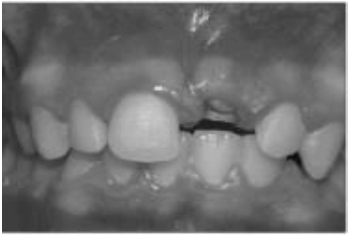

Observe a imagem a seguir:

Qual dente decíduo sofreu avulsão na imagem acima?